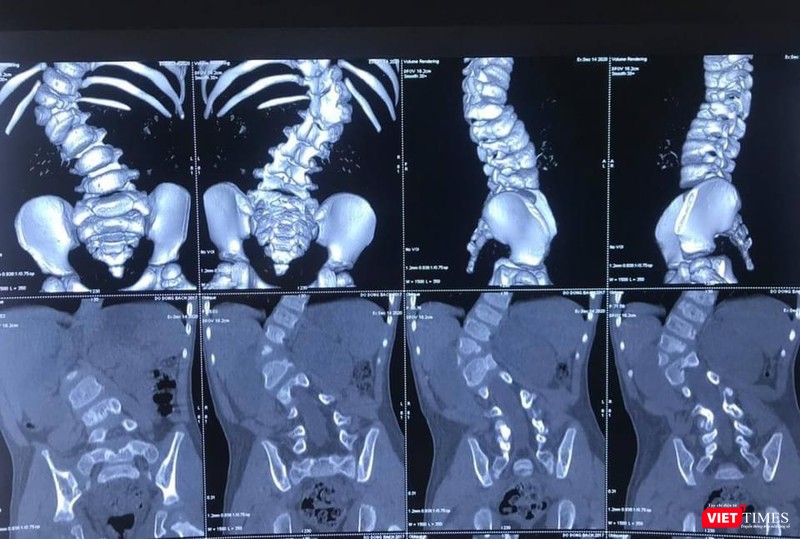

Bé B.Đ mới 3 tuổi được bố mẹ phát hiện có bất thường tại cột sống ngay từ khi mới 2 tuổi. Đưa con đi khám, gia đình được biết em bé bị vẹo cột sống ngực – thắt lưng bẩm sinh mức độ lớn do dị tật nửa đốt sống L1. Bé vẫn đi lại được nhưng cột sống lệch vẹo, cúi ngửa khó khăn, hạn chế vận động do đau lưng.

Năm nay bé 3 tuổi, tình trạng biến dạng cột sống của bệnh nhi B.Đ đã là mức độ nặng, góc vẹo 66 độ. BS chuyên khoa chẩn đoán cho biết nếu trì hoãn mổ, đến khi bệnh nhi được 6 tuổi trở lên thì sẽ không thể phẫu thuật nắn chỉnh được dị tật vẹo cột sống, nguy cơ bệnh nhi sẽ mất đi cả cuộc sống bình thường. Vi thế, bố mẹ bé đã quyết định đưa bé nhập viện vào khoa Chấn thương - Chỉnh hình Cột sống (Bệnh viện 108).

Bác sĩ chuyên khoa cho biết vẹo cột sống bẩm sinh là biến dạng vẹo của cột sống do sự phát triển bất thường của cột sống ngay từ khi trẻ em sinh ra. Hai nguyên nhân chính của vẹo cột sống bẩm sinh là bất thường về sự phân chia đốt sống, bất thường về hình thành đốt sống hoặc kết hợp cả hai nguyên nhân. Mức độ tiến triển biến dạng gù vẹo cột sống rất dao động tùy theo vị trí đốt sống phát triển bất thường. Một số trẻ có đường cong vẹo ổn định và không thay đổi theo thời gian, trong khi đó có trẻ em biến dạng vẹo tiến triển không ngừng.

| Hình ảnh X quang ca cong vẹo cột sống của bệnh nhi 3 tuổi (BVCC) |

Thông thường, các bác sĩ chuyên khoa chỉnh hình cột sống sẽ theo dõi tiến triển của đường cong vẹo bằng cách chụp X-quang cứ 6 tháng một lần. Nếu góc vẹo cột sống tiến triển thì cố gắng trì hoãn phẫu thuật đến khi các cháu bé được trên 6 tuổi. Vì khi đó, bệnh nhi đủ lớn để gây mê hồi sức và phẫu thuật an toàn hơn.

Tuy nhiên, cũng có những dị tật cột sống ngay từ rất sớm đã gây ra biến dạng rất lớn của cột sống nên cần phải can thiệp điều trị phẫu thuật sớm để ngăn chặn và nắn chỉnh biến dạng. Trong trường hợp này, những tai biến biến chứng của phẫu thuật và gây mê hồi sức sẽ cao hơn.

Về mặt phẫu thuật, đây là trường hợp cháu bé còn rất nhỏ tuổi nhưng đã có biến dạng cột sống rất lớn, góc vẹo cột sống T11-L2 66 độ, có dị tật nửa thân đốt L1 bên phải, thiểu sản cuống sống T12 bên phải. Do vậy, tính chất cuộc phẫu thuật rất phức tạp.